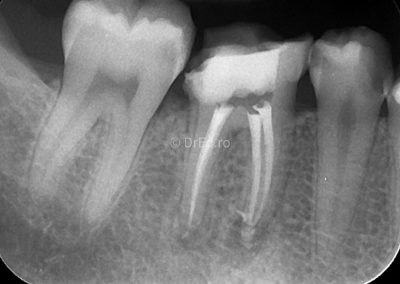

Galerie

Toate imaginile, fotografiile și radiografiile publicate pe acest site sunt protejate prin drepturi de autor și constituie proprietatea exclusivă a Dred.ro.

Aceste materiale sunt furnizate exclusiv în scop informativ și educațional și nu conțin date cu caracter personal sau informații care permit identificarea pacienților, în concordanță cu legislația privind protecția datelor cu caracter personal și GDPR.

Reproducerea, copierea, distribuirea, publicarea, transmiterea, modificarea sau orice altă utilizare, integrală ori parțială, a acestor materiale, în orice formă și prin orice mijloace, fără consimțământul prealabil scris al titularului drepturilor, este strict interzisă și poate atrage răspunderea civilă și/sau penală, în condițiile legii aplicabile privind drepturile de autor și protecția proprietății intelectuale.